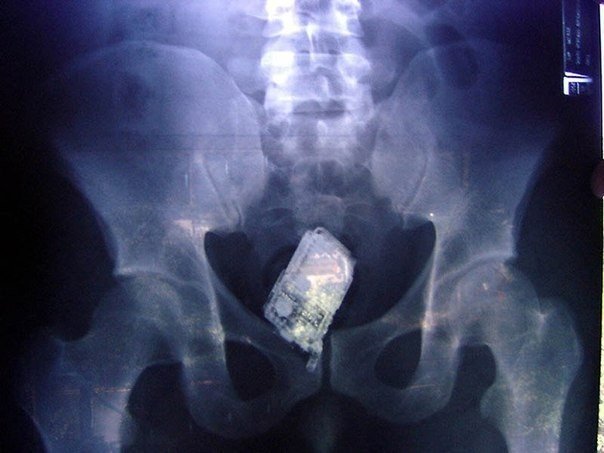

Самые причудливые рентгеновские снимки в истории медицины. Некоторые из них жуткие и пугающие, возможно часть из них вызовет у вас шок. Трудно поверить в то, что это правда, однако снимки говорят сами за себя.. 1) Череп китайского мужчины, который был уби8 写真